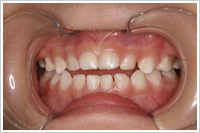

●4歳11か月

ず~と指しゃぶりをしている幼児

お母さんがどんなに注意をしてもやめません。手袋をして寝ても、寝ながら手袋をはずして指しゃぶりをします。指にわさびやからしをぬったら、夜中が大変。指に糸を巻きつけても駄目です。口が開いているので喉が弱く、よく風邪をひいたり、鼻炎になったりでお母さん(お父さんも)がたいへんでした。

●5歳5か月

指しゃぶり防止グローブをはめて約1週間で指しゃぷりをやめました。その後約6か月で、歯並びが正常になりました。 鼻炎もなくなりお医者さん通いが少なくなりました。何より顔つきがよくなりました。夜もぐっすり眠れるようになりました。これで治れば高額な矯正治療は必要ありません。